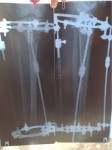

Ножки на фиксации, всё ок! Уезжаю домой на сращение!

Ножки на сегодня!